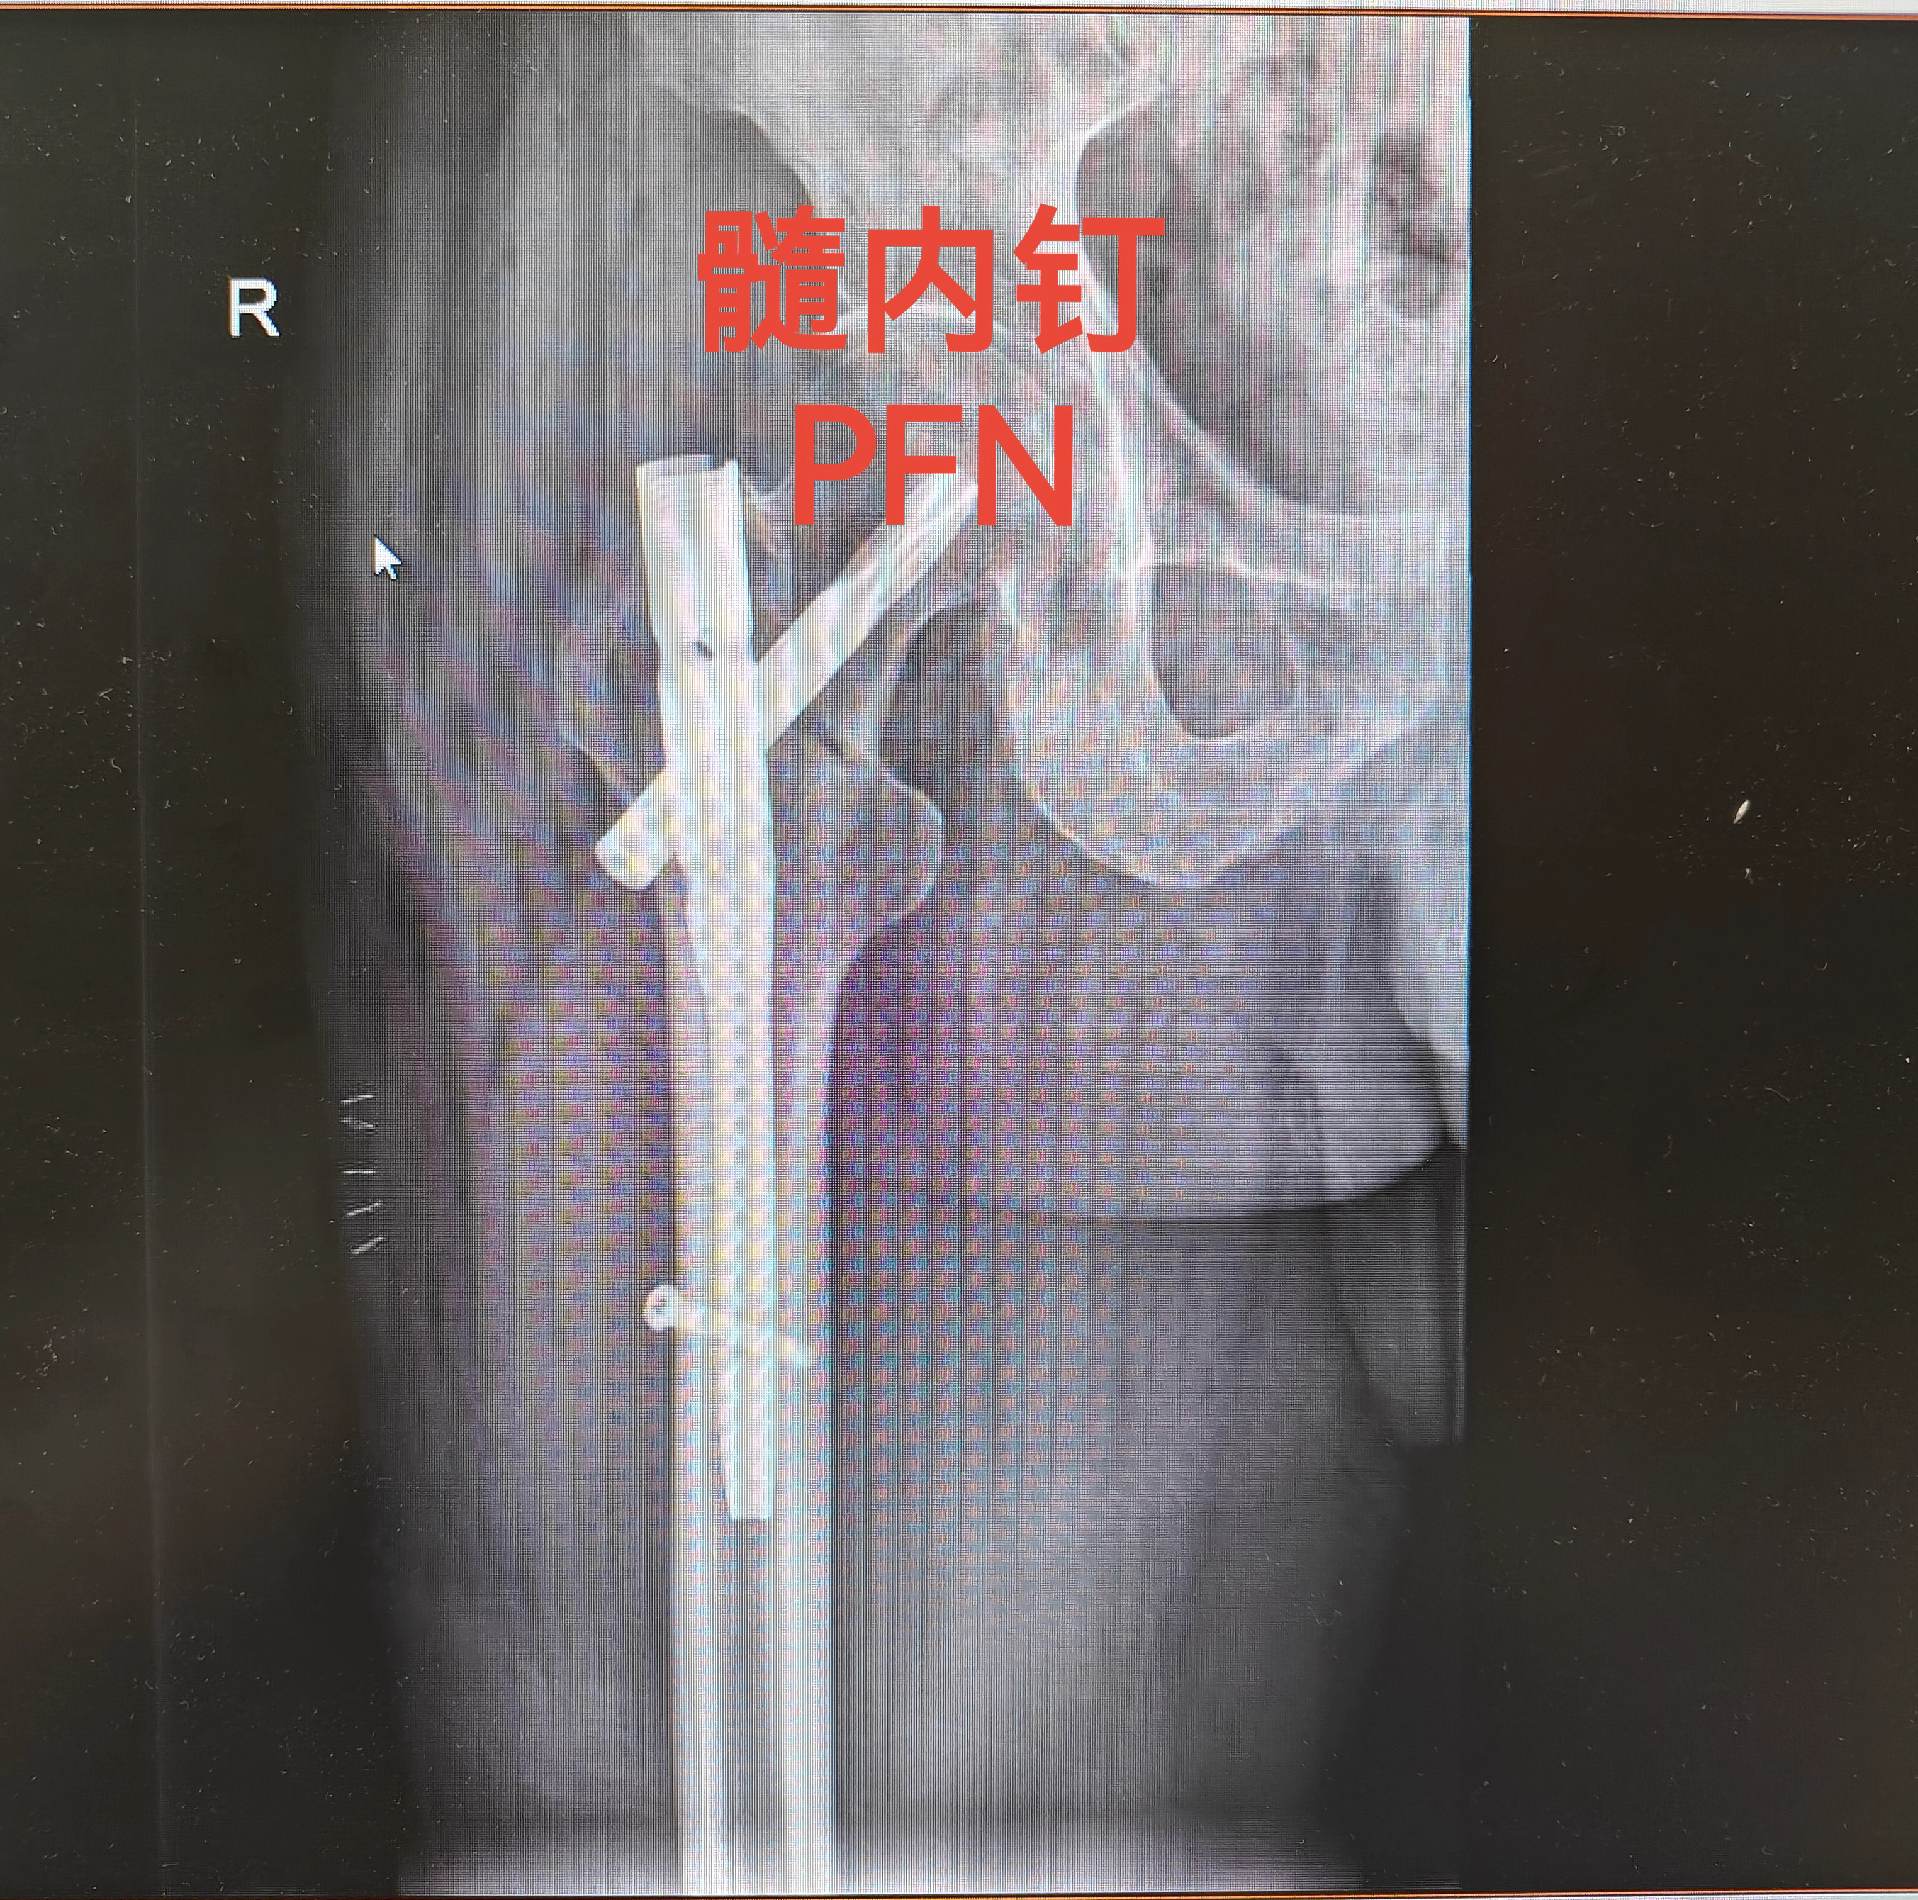

假体周围骨折。髋关节置换术后假体周围骨折,再次翻修,关注老年患者骨质疏...